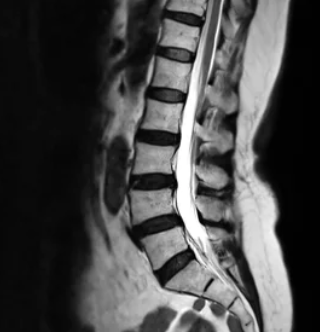

허리디스크, 또는 요추 추간판 탈출증은 척추 뼈 사이의 디스크가 손상되어 신경을 압박하는 질환입니다. 이 상태는 통증, 마비, 감각 이상 등 다양한 증상을 유발할 수 있으며, 일상 생활에 큰 지장을 줄 수 있습니다. 허리디스크의 증상은 개인마다 다르게 나타나지만, 일반적으로 몇 가지 공통적인 증상들이 있습니다.

허리디스크로 인한 다리저림은 흔히 겪을 수 있는 증상 중 하나입니다. 이는 척추의 디스크가 탈출하거나 돌출되어 신경을 압박함으로써 발생합니다. 특히, 척추의 하부인 요추 부위에 문제가 생겼을 때 다리에 저림이나 통증을 느낄 수 있습니다. 이러한 증상은 장시간 앉아 있거나 서 있을 때 더욱 심해질 수 있으며, 때로는 걷거나 서 있는 것조차 어렵게 만들 수 있습니다.

중요한 것은 적절한 진단을 받는 것입니다. 의사는 환자의 증상을 평가하고 MRI나 CT 스캔과 같은 영상 진단을 통해 허리디스크의 정도를 확인할 수 있습니다. 이를 통해 가장 적합한 치료 방법을 결정할 수 있습니다.